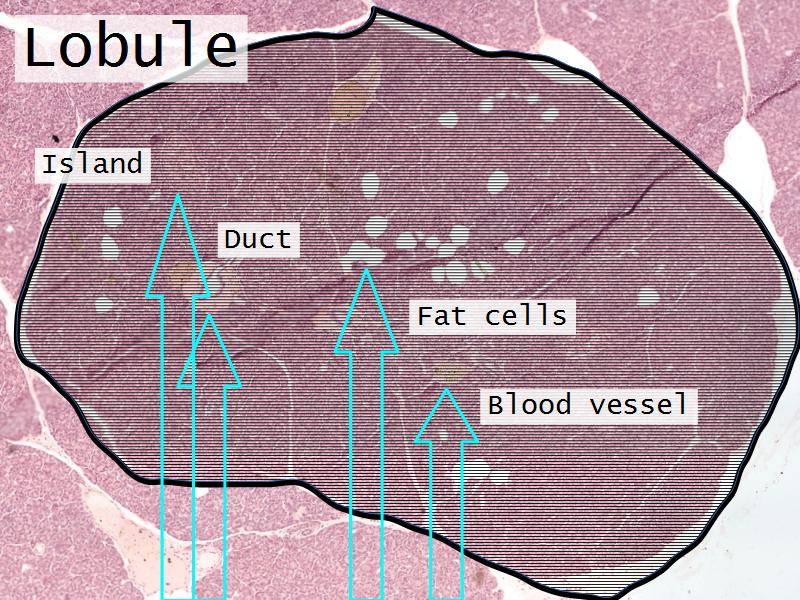

- Pancreas

- C3: Pancreas

- C3: Pancreas = glucagon, insulin, somatostatin, pancreatic polypeptide

- F4: Alpha cells = pancreas

- Slide 50: Pancreas